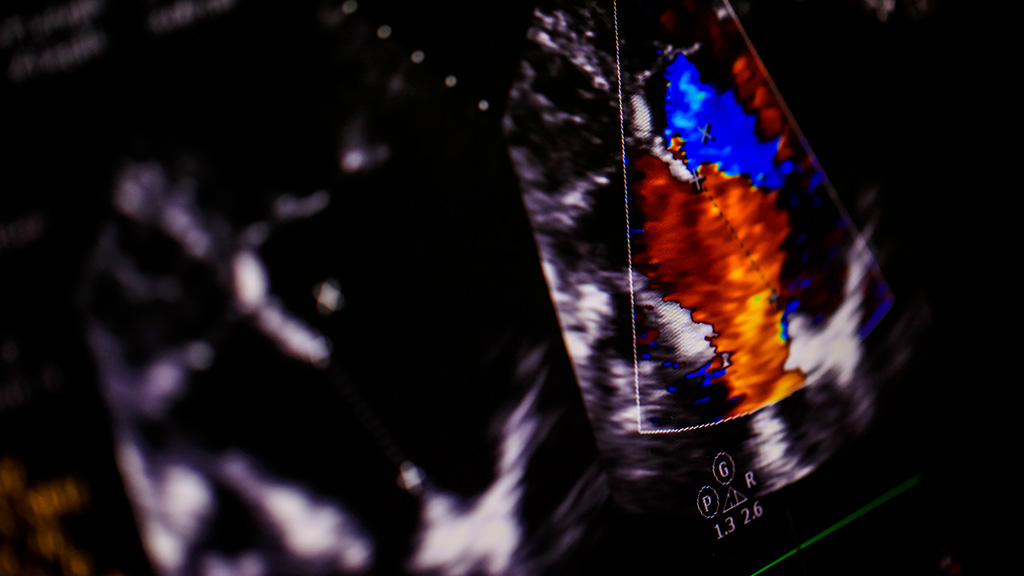

Ultrasonido Doppler Color Mama (Bilateral)